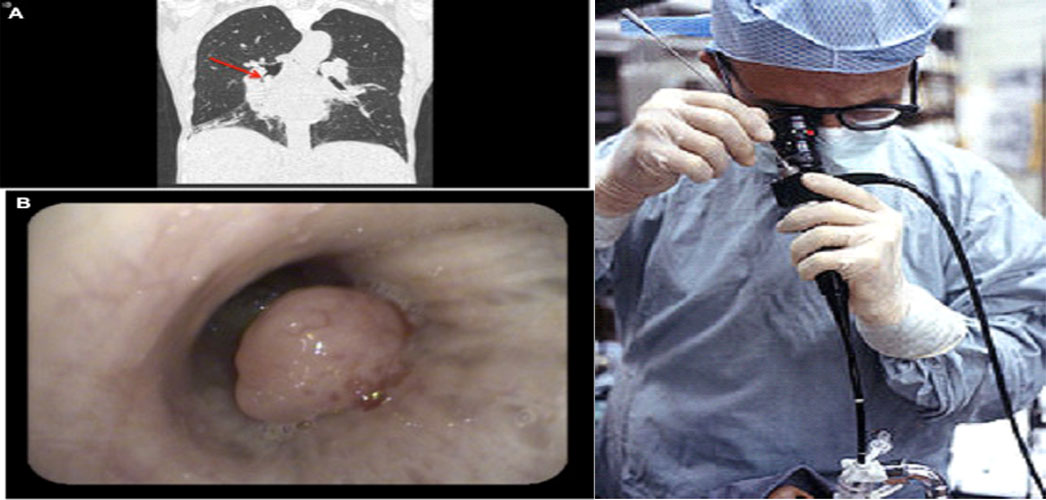

Αποτελεί μια ιατρική πράξη που επιτρέπει με τρόπο άμεσο και αξιόπιστο την εξέταση των πνευμόνων. Απαραίτητη προϋπόθεση είναι να διενεργείται από κατάλληλα εκπαιδευμένο γιατρό. Πραγματοποιείται με την είσοδο, συνηθέστερα από τη μύτη και σπανιότερα από το στόμα, ενός λεπτού σωλήνα με κάμερα, στο εσωτερικό των πνευμόνων (τραχεία, βρογχικό Δένδρο).

Διαγνωστική βρογχοσκόπηση: ο βρογχοσκόπος κατευθύνει το βρογχοσκόπιο στην περιοχή με τη βλάβη από την οποία λαμβάνει βιοψίες, συλλέγοντας βρογχικές εκκρίσεις και κυτταρολογικό υλικό, τα οποία αποστέλλονται για μικροσκοπική εξέταση και μπορεί με αυτόν τον τρόπο να δώσει διάγνωση σε πληθώρα παθήσεων.

(λοιμώξεις, κακοήθειες, διάμεσα νοσήματα).